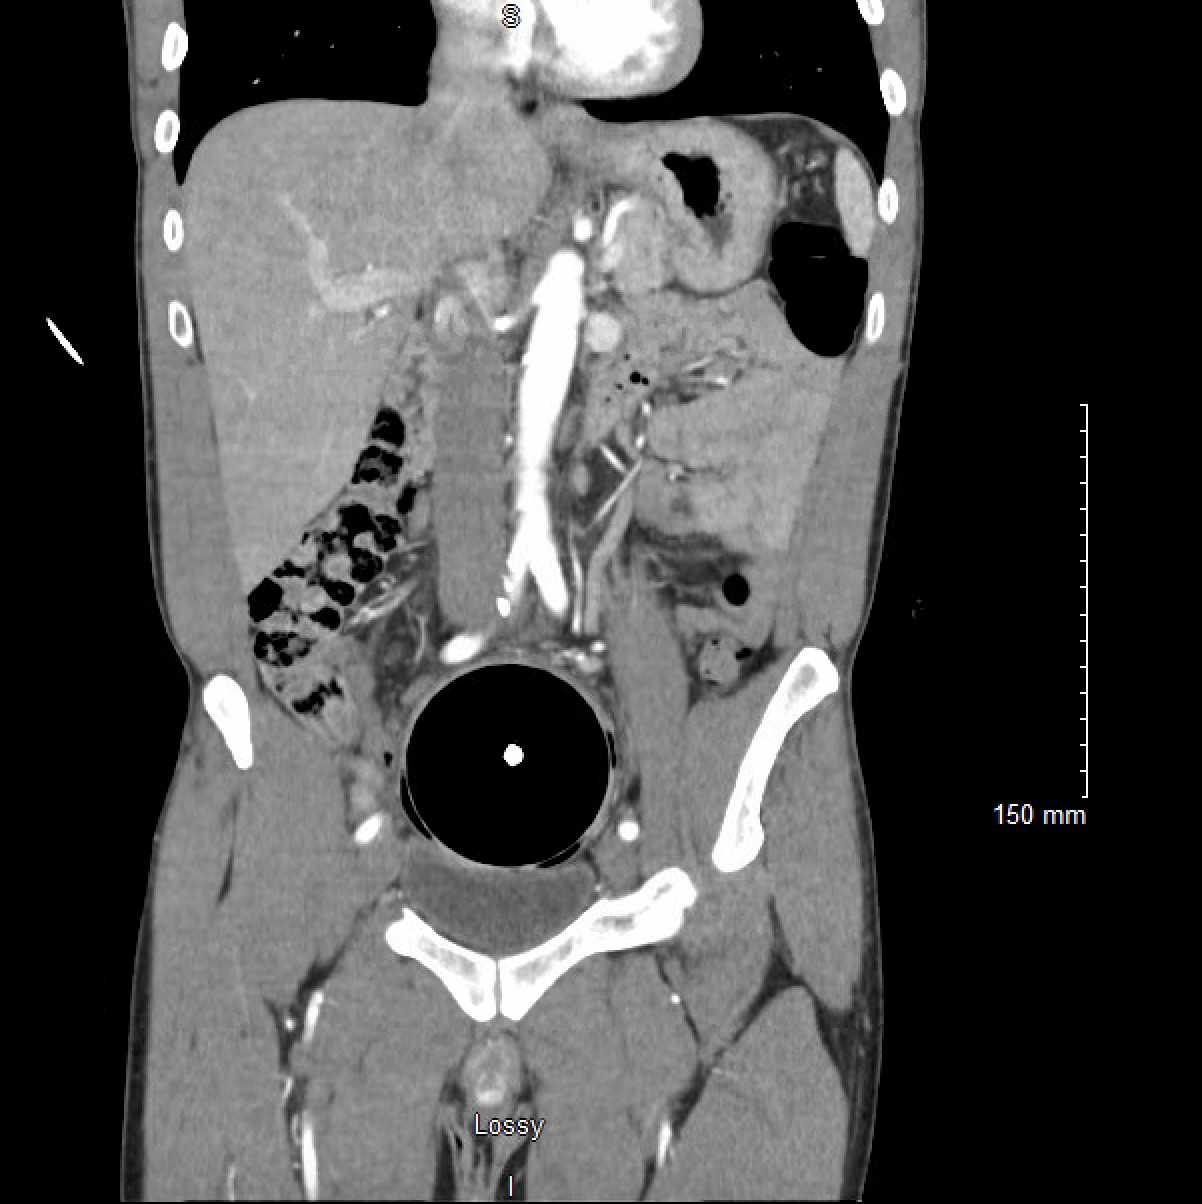

An adult male presented to the Emergency Department with a retained rectal object. On presentation, the patient was clinically stable, though he reported feeling constipated and bloated after four days with the object in situ. A CT abdomen and pelvis with intravenous contrast was performed which demonstrated a 8.2 cm spherical foreign body in the distal sigmoid colon with thickening of the distal sigmoid colon and rectum. There was no evidence to suggest perforation. (Figures 1-2) The retained object was a sphere made of hard plastic with a light inside. A chain attached to the sphere had broken off–not allowing the patient to remove the object himself. Initial attempts made to evacuate the object in the emergency department included the use of an obstetric vacuum delivery system; however, the patient was unable to tolerate these attempts. He was then taken to the operating room for removal under general anesthesia. In the dorsal lithotomy position, the sphere was able to be palpated. Given the hard material of the object, it was not able to be grasped or penetrated with Kocher clamps or myoma screws. An obstetrical vacuum was able to guide the object caudally into the rectum, but the vacuum was not able to fully extract the object. Ultimately, an obstetrician-gynecologist applied Tucker McClane obstetric forceps around the object and was able to successfully deliver the sphere. A general surgeon subsequently performed endoscopy to confirm there were no rectal or sphincter lacerations. The patient was able to be discharged home the same day.